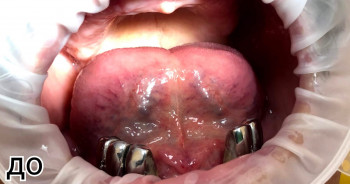

Конушкин Данил Юрьевич: портфолио (1)